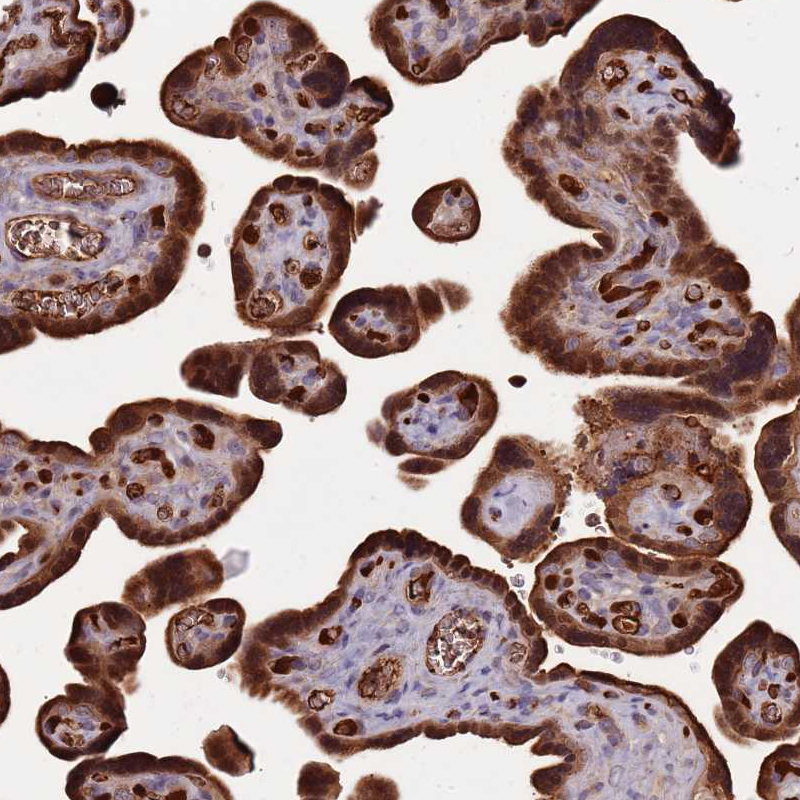

Immunohistochemical staining of human placenta shows strong cytoplasmic positivity in trophoblastic cells.